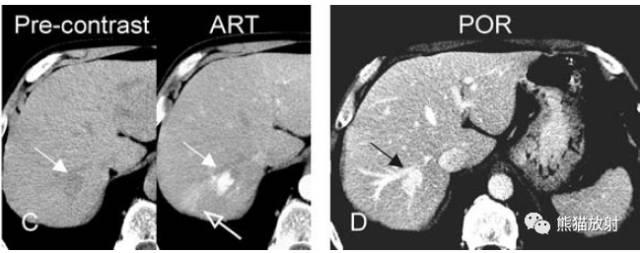

各序列信号特征:

T2 fatsat:T2压脂,明亮高信号;

T1 in-phase:T1同相位,低信号;

ART:动脉期,肿瘤大部分明显均匀强化(实心箭),周围可见轻微强化区(空心箭);

DEL:延迟期,血管瘤均匀持续强化。

A~D:影像表现如上所述。

图A、B:因肝功能异常行超声检查,右叶可见一异常回声;

图C、D:CT平扫呈低密度,动脉期明显全瘤性强化,周围肝实质可见片状一过性强化区,门脉期肿瘤均匀持续强化。CT未给出明确诊断,建议进一步MR扫描(如前面所示)。